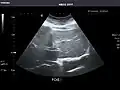

Right kidney